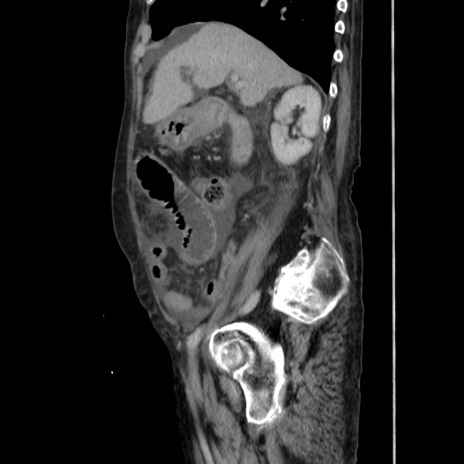

症例31(矢状断像)

【症例】80歳代 女性

【主訴】腹部膨満感

【現病歴】他院にて肝硬変にてフォロー中。1週間前から便秘、腹部膨満感、臍部腫瘤あり受診となる。

【既往歴】肝硬変

【身体所見】腹部膨隆あり、皮膚変化なし、疼痛なし。

【データ】WBC 4600、CRP 0.25